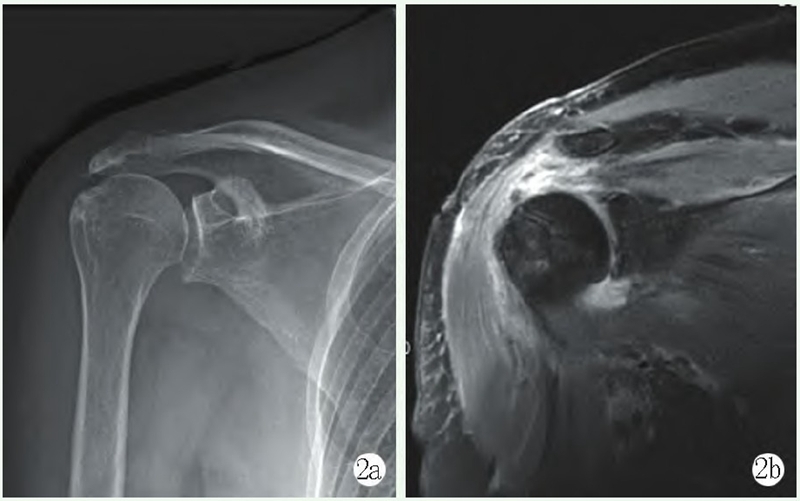

影像学检查:X线片显示左肱骨头解剖颈处小骨片(图1a),彩超示:左肱骨头解剖颈处小撕脱骨片。

1a:术前肩关节正位 X 线片示左肱骨头解剖颈处小骨片

手术:采用全麻联合臂丛神经阻滞麻醉。右侧卧位左肩外展牵引下手术。左肩关节后方及前方建立关节镜手术入路,关节镜探查盂肱关节见盂唇附着完好,肱骨头关节面边缘冈上肌附着处可见全层软骨及软骨下骨撕脱骨折片5~6mm,冈上肌从肩关节撕裂(图1b)。置入带线锚钉通过Trans-Tendon法用腰穿针将锚钉尾端缝线穿过冈上肌后打结固定骨折块(图1c)。

图1b: 镜下见冈上肌关节面横行撕裂;1c: 置入锚钉,用腰穿针将锚钉尾端缝线穿过冈上肌后打结固定骨折块